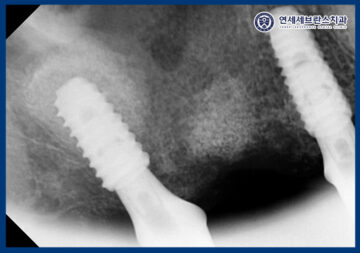

CT로 비교해 보았을 때,

상악동거상술을 통해

부족했던 상악동 하방 공간을 확보하여

임플란트 식립이 가능한 환경을

조성한 것을 확인할 수 있었습니다.